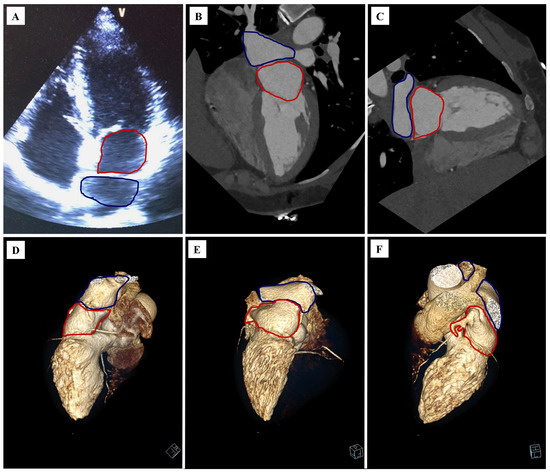

Coexistence of Cor Triatriatum Sinister, Fibroelastoma and Pulmonary Veins Ostial Anatomy Variant as Incidental Findings in Coronary Computed Tomography Angiography